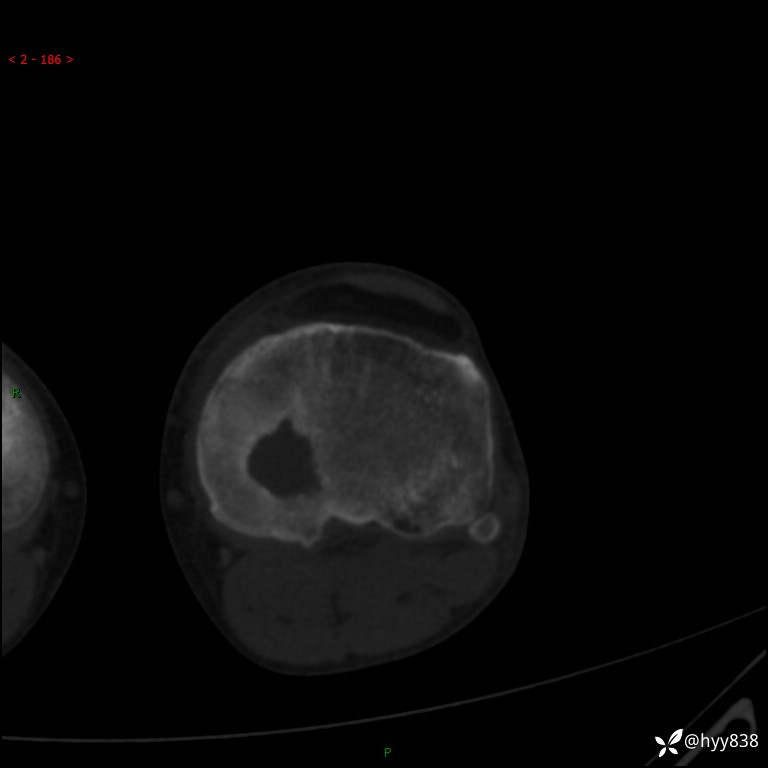

CT